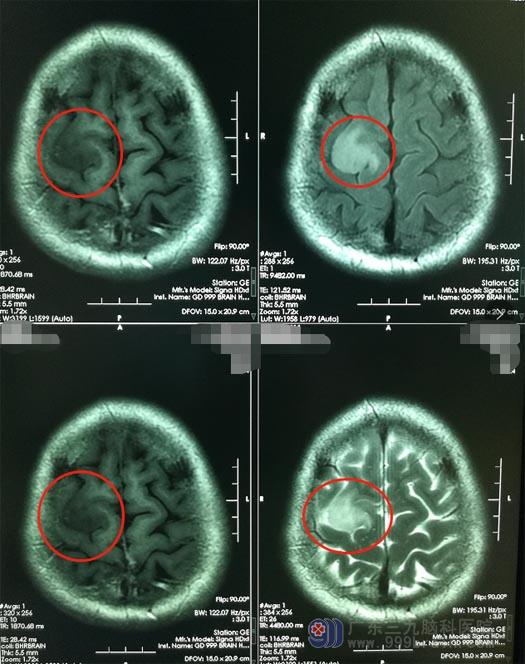

充分的术前准备后,鲁明带领团队为钟叔行“唤醒麻醉下右侧额叶病变切除术”,术中,利用电生理及唤醒麻醉技术,在显微镜下避开脑功能区,完整地切除了肿瘤。

术后的钟叔语言和四肢活动功能正常。家人说:再也不用活在癫痫的阴影下了。